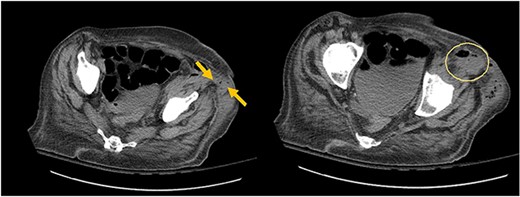

A 73-year-old female with past medical history of hypertension, diabetes mellitus, hyperlipidemia, recent history of complicated sigmoid diverticulitis with psoas abscess measuring 1.4 cm × 6.5 cm (Images 1 and 2). Patient underwent interventional radiology drain placement in the abscess cavity and antibiotic treatment with adequate response and was discharged home with oral antibiotics. Her last colonoscopy was 1 year prior, with no evidence of polyps. She followed up after 10 days with our colorectal surgeon. She denied any pain, her drain output was minimal. She was offered surgical intervention, however she refused. Drain was removed. She presented to the hospital again after 3 weeks with lower abdominal pain with radiation to left back and with anterior left upper thigh pain. She felt a sensation of fullness in that area. She was tolerating diet and having normal bowel movements. She denied any fevers, chills, urinary complaints. On the physical exam, her abdomen was soft, non-distended, there was tenderness to palpation in her left lower quadrant, no rebound, no rigidity. There was also severe tenderness to palpation in the left antero-lateral thigh. There were no skin changes, crepitus to palpation or drainage from this area.

Arrows shows extension of psoas abscess through abdominal wall in the surrounding tissues around the hip. There is not Hip bone involvement. Circle shows abscess next to the hip.